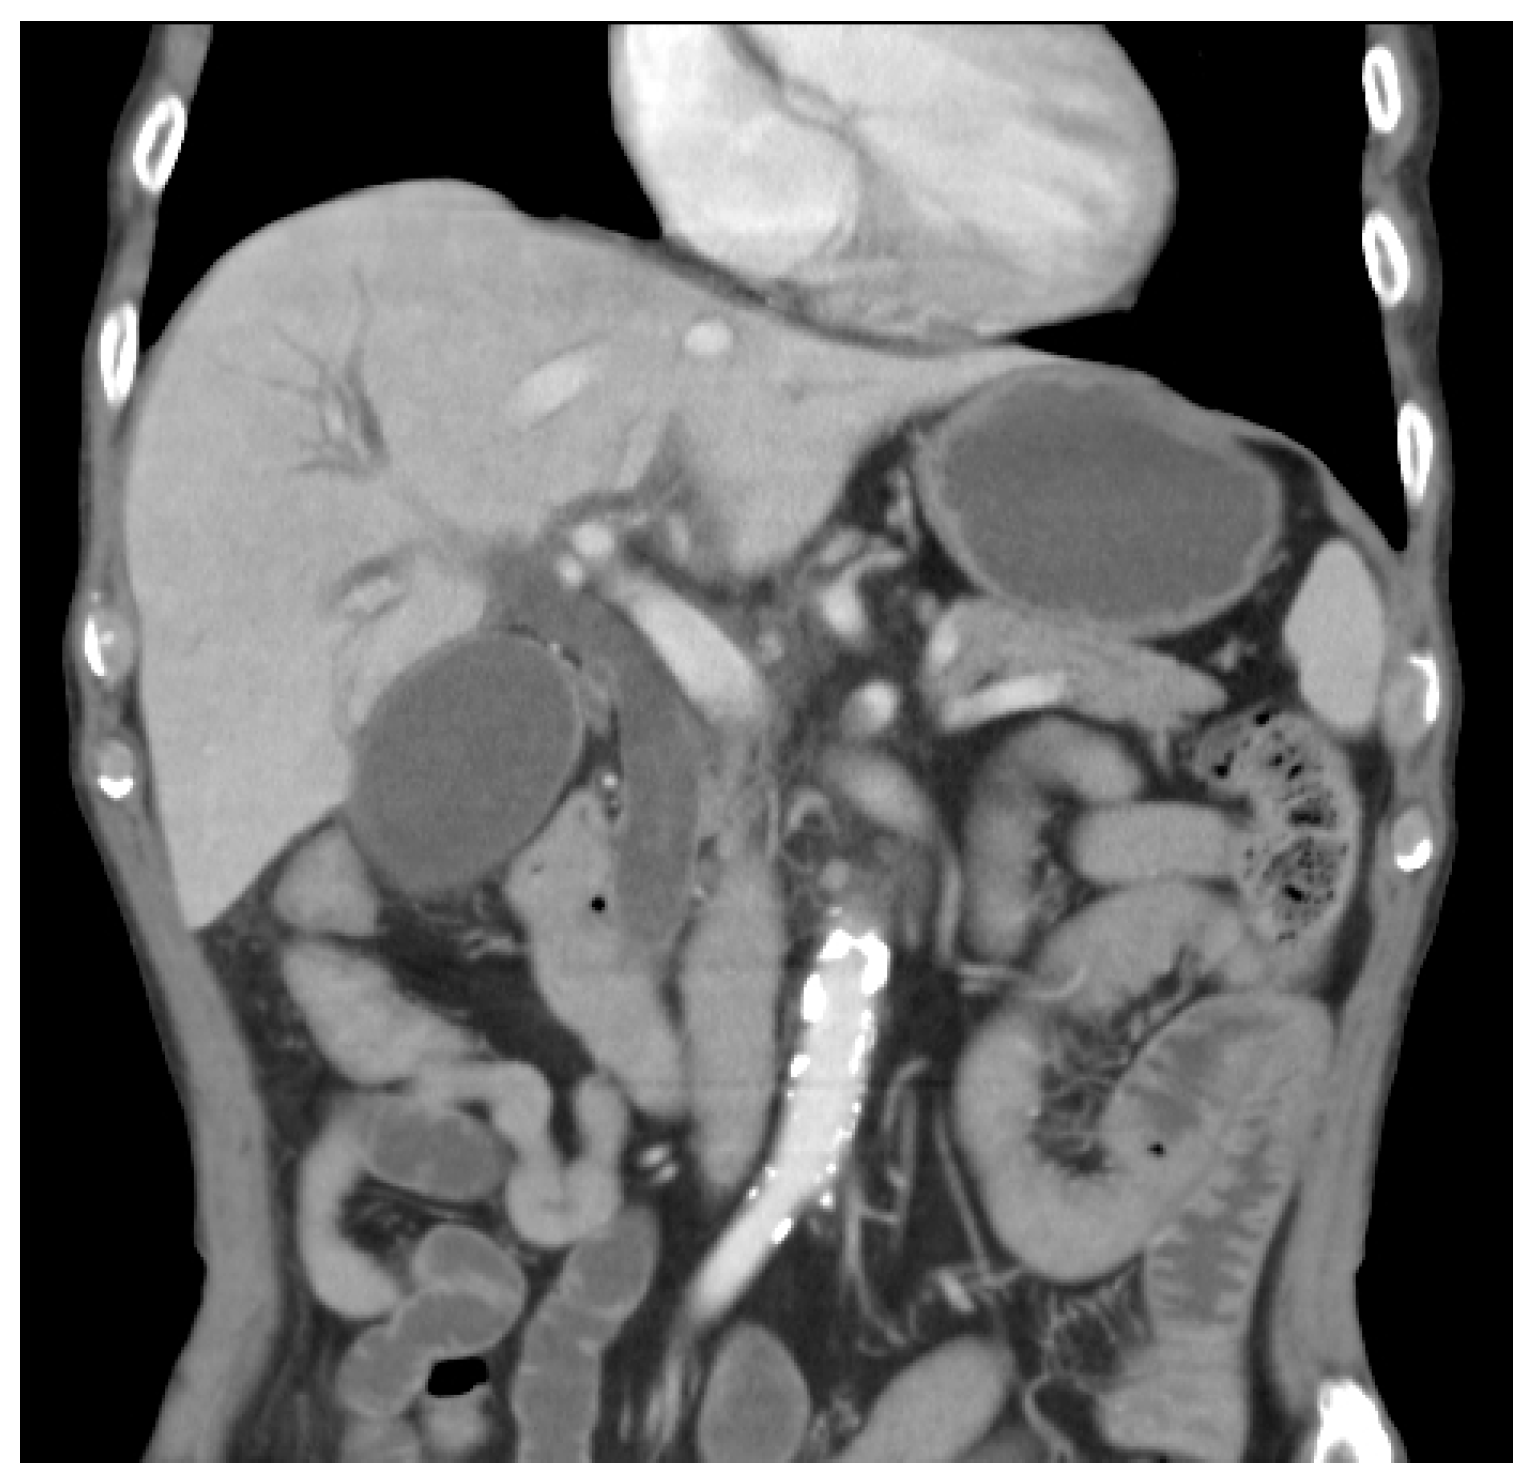

2.2. TAE Procedure